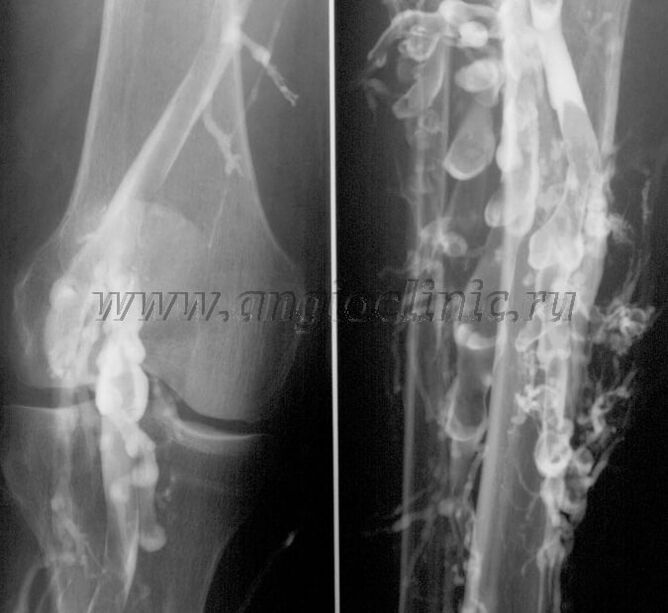

Kontrastne venograafia

Tavaliselt piisab veenipatoloogia täielikuks diagnoosimiseks ultraheliuuringust, kuid mõnel juhul on vaja uurida süva- ja pindmiste veenisüsteemi seisundi seost, eriti veenilaiendite ja sekundaarsete veenilaiendite ägenemiste korral.

Nende probleemide lahendamiseks kasutatakse kontrastset röntgenuuringut. Safeenveenid torgatakse ja manustatakse kontrastainet. Kontrastsuse liikumist jälgitakse röntgeniaparaadi monitoril ning tehakse kõik vajalikud testid ja projektsioonid. Praegu kasutatakse veenilaiendite venograafiat väga harva.